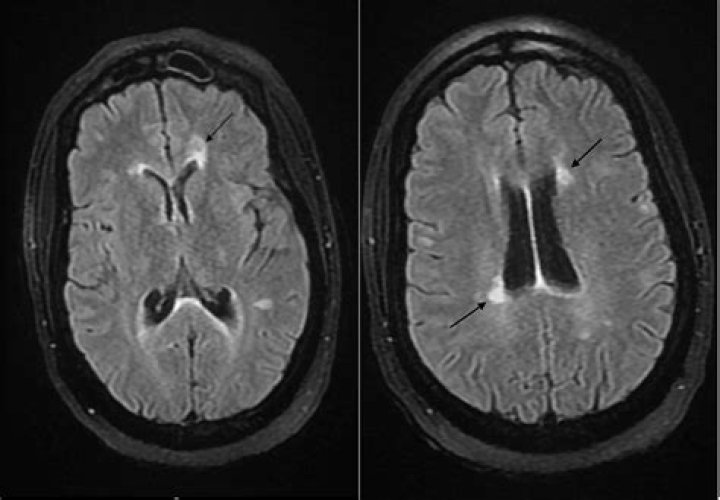

Where does demyelination occur in multiple sclerosis (MS)?

In MS, demyelination occurs in the white matter of the brain and in the spinal cord. Lesions or “plaques” then form where myelin is under attack by the immune system. Many of these plaques (or scar tissue) occur throughout the brain over the course of years.